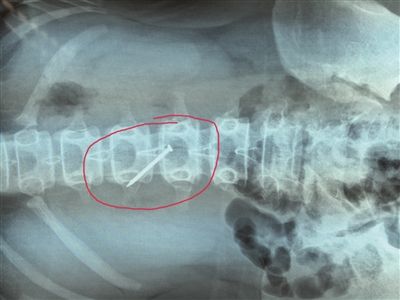

長約4厘米的鐵釘被取出時,已刺穿13歲女生的胃壁。 朱鼎兆 攝

一根長近4厘米的鐵釘在胃里會怎么樣?29日下午4時許,在淮安市婦幼保健院,該院小兒科醫(yī)生就從宿遷泗陽一名13歲女生小軒(化名)的胃里成功取出一根長約4厘米的鐵釘,而此時,這根鐵釘已經(jīng)刺破了小軒的胃壁。